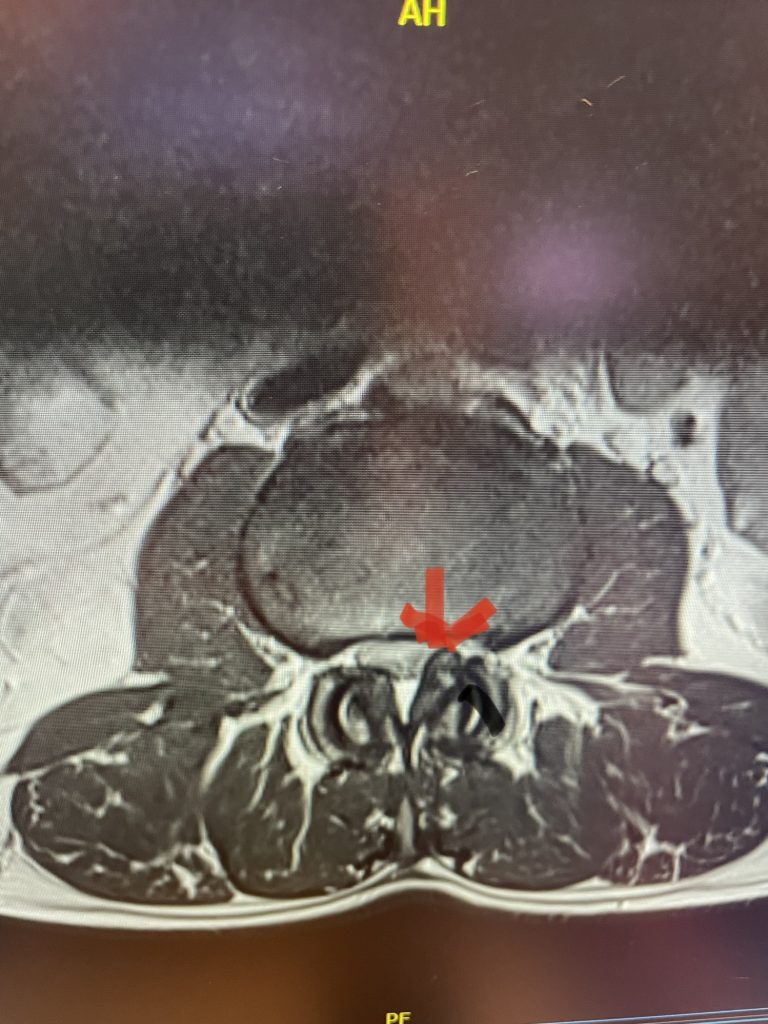

Lateral recess stenosis typically involves compression of the nerve root as it takes off from the thecal sac, prior to entering the nerve foramen or tunnel. In lateral recess stenosis there is narrowing of less than 5 mm between the facet superior articulating process and the posterior vertebral margin and is bounded laterally by the pedicle. The nerve root gets caught medial to the pedicle. The nerve is compressed commonly from thickened ligamentum, short pedicles, or in particular an enlarged superior facet process which compresses the nerve as it descends prior to going underneath the pedicle in a region that is designated as the subarticular recess. (Figs 1, 2, and 3) With lateral recess stenosis, for example, of the L4-5 subarticular recess, the descending L5 nerve root will be compressed by the corresponding L5 superior facet. With foraminal stenosis the actual nerve root is compressed beyond the medial pedicular zone which can be caused by a far lateral type disc facet hypertrophy, tumor, or subluxation.

Figure 1: Axial lumbar spine images demonstrating the descent of the nerve root below the subarticular recess as it rounds the pedicle and enters the neural foramen. On the left shows the normal anatomy and on the right showing the descending nerve root being compressed in the lateral recess by a hypertrophied superior process with medial protrusion.

Figure 2: Cartoon axial image of the lumbar spine showing (arrow) severe narrowing of the lateral recess with flattening of the nerve root compared to a normal nerve root on the opposite side.